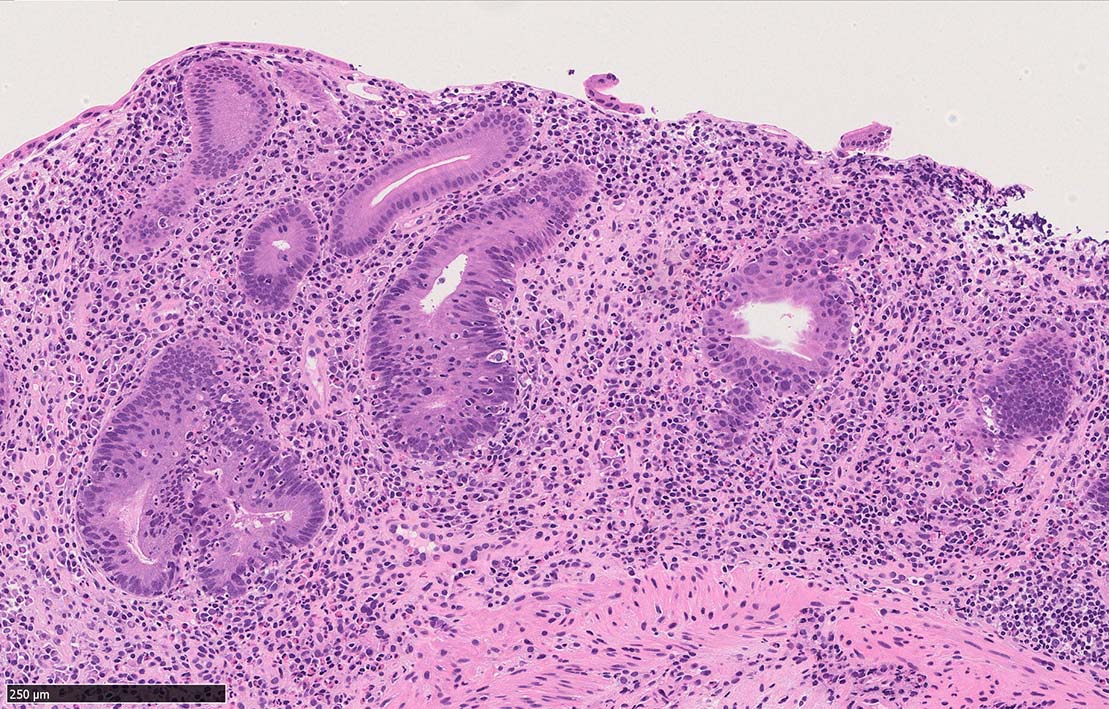

Case presentation

びらんを示す結腸粘膜. 陰窩はdeletion, 萎縮, distortionを呈する. 粘膜固有層には密な慢性炎症がみられ, 好酸球浸潤も多い.粘膜筋板へも炎症細胞浸潤が及ぶ.

UCのような, crypt abscess, cryptitisが認められる. 特徴的な所見として, apoptosis bodiesの増加が見られる.